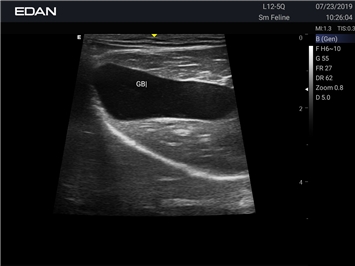

Ветеринарный ультразвук одним нажатием. Система Acclarix AX2 VET разработана с целью обеспечить бескомпромиссную производительность по доступной цене. Наличие уникальных двойных аккумуляторов в легком корпусе массой 4,5 кг из магниевого сплава позволяет системе Acclarix AX2 VET удовлетворять все потребности ветеринарных исследований, сохранив низкую стоимость.

EDAN Acclarix AX2 VET представляет собой специализированную ветеринарную ультразвуковую систему, сочетающую высокую производительность с доступной ценой. Благодаря продуманной конструкции и передовым технологиям, система обеспечивает качественную диагностику животных различных видов.

• Высокое разрешение для детальной диагностики

• Улучшенная визуализация глубоко расположенных органов

• Непрерывная автоматическая оптимизация изображения

• Адаптация к особенностям анатомии разных видов животных

• Повышенная точность исследований

• Предустановленные протоколы для различных видов животных